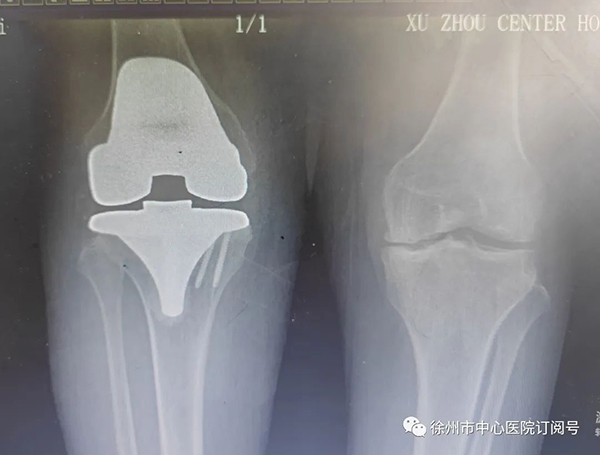

最終,那鍵團(tuán)隊(duì)結(jié)合影像資料,患者癥狀,實(shí)驗(yàn)室檢查等決定對(duì)潘女士施行右膝全部膝關(guān)節(jié)置換術(shù)。

(手術(shù)前后影像對(duì)比)

術(shù)中,發(fā)現(xiàn)患者股骨、脛骨、髕骨軟骨廣泛剝脫,髕骨關(guān)節(jié)軟骨下骨裸露,邊緣有大量骨贅形成,內(nèi)外側(cè)半月板退變,邊緣毛糙,關(guān)節(jié)腔內(nèi)可見(jiàn)大量淡黃色滑液,滑膜增生肥厚。那鍵憑借豐富的臨床經(jīng)驗(yàn),將患者右膝關(guān)節(jié)全部置換,手術(shù)順利完成。

術(shù)后,潘女士的腿恢復(fù)了正常,完全和正常人一樣可以伸直、彎曲。術(shù)后幾天,便可下床走路。潘女士及家人對(duì)手術(shù)效果十分滿意,連連向那鍵道謝。